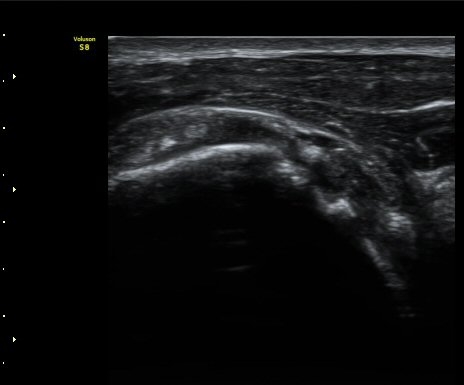

ŽÃÊÀÚ¸¦ ¾à°£ ´Ù¸®ÂÊ, ³»ÃøÀ¸·Î À̵¿ÇÏ´Ï °ß°©ÇÏ±Ù°Ç Ç¥Ãþ¿¡ ¸¹Àº ¾çÀÇ ¼ö¾×Àú·ù°¡ °üÂûµÈ´Ù(»çÁø 3).

ÆÈÀ» ¿ÜȸÀüÇÏ´Ï °ß°©ÇÏ±Ù°Ç Ç¥ÃþÀÇ ¼ö¾×Àú·ù°¡ ´õ¿í È®½ÇÇÏ°Ô °üÂûµµ´Ï´Ù(»çÁø 4).